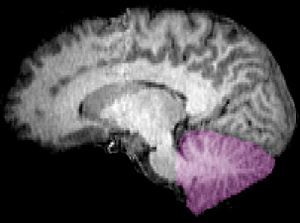

很久以来人们一直以为小脑的主要功能是支配肢体动作协调性。然而本月发表在《神经元》(Neuron)期刊上的研究发现,小脑的作用可远不止这个方面,小脑“插手”高层次大脑功能的几乎每个方面,包括注意力、思考、计划和决策,扮演着最后审查这些大脑活动的角色。

他们在小脑中找不到关于感官处理的网络,比如视觉、听觉和触觉,只有20%的小脑致力于控制肢体行动,这与大脑皮层的情况类似。小脑剩余80%的功能都在处理高级认知任务:控制注意力;和没有特别集中注意力时候的工作,比如做“白日梦”、回味记忆、或漫无目的“胡思乱想”;以及执行监控决策和计划功能。

研究者们测量了大脑活动的时间周期,发现小脑的参与时间点正符合“把关”的最后决策角色。感官系统收到信号,立即在大脑皮层中进行处理,然后送给小脑。研究者们猜想,正是在小脑,这些信号得到最后的“质量检查”,最后送回给大脑皮层进行实施。